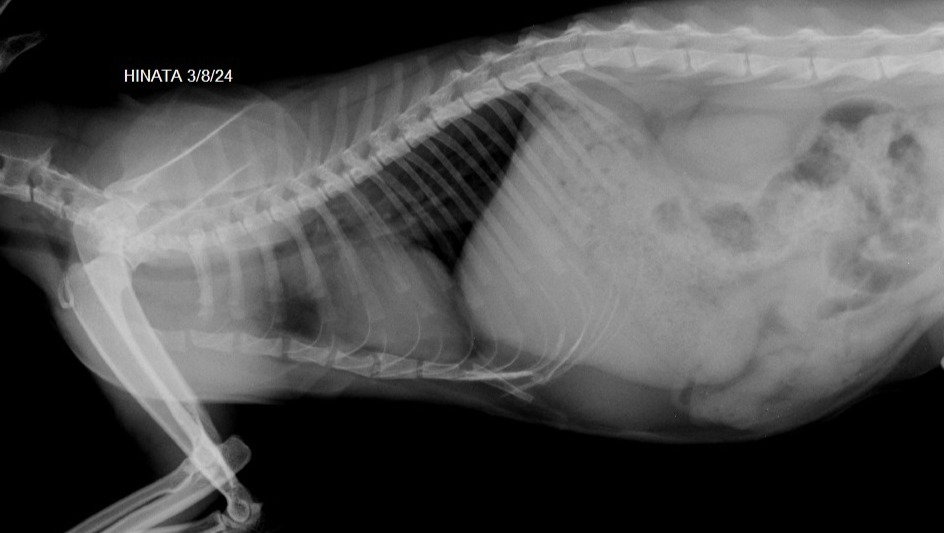

Turns out the mass is located on her mediastinum, and it has to be surgecally removed.

Since the mass in her mediastinum is getting bigger, she is having trouble digesting properly the food and also has hard time breathing coz of the pressure.

this is the study of her tumors in her jaw and the rest of ultrasound, ecocardio and torax.